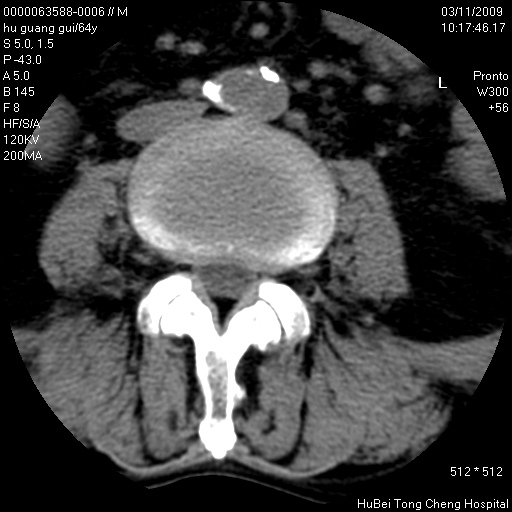

患者 男,64岁。腰痛十余天。(临床未提供其他病史)

临床诊断:腰痛原因待查(腰椎间盘突出症?)。

腰椎间盘ct轴位平扫(层厚5mm,层距4mm),图像如下:

腰椎退行性变,腰4—5椎间盘膨出。

右侧骶骨侧块骨侵蚀,骶髂关节骨性关节面破坏,并见软组织肿块,考虑骨转移瘤可能,进一步检查。

1.腰椎退行性变,腰4—5椎间盘膨出。

2.右侧骶骨侧块骨侵蚀,骶髂关节骨性关节面破坏,并见软组织肿块,考虑:脊索瘤,骨转移瘤可能,进一步检查。

1)腰椎退行性变,l4—5椎间盘膨出。2)骶骨右侧块骨转移瘤可能,3)水平骶椎。建议作一步检查。